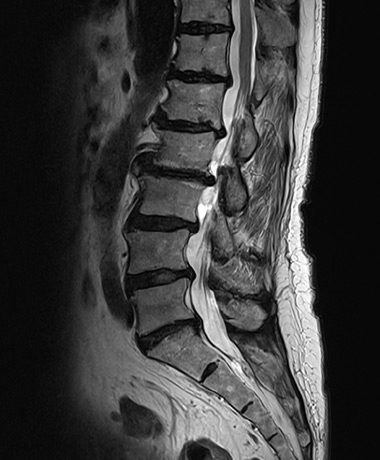

통증의 원인을 정확하게 진단

척추·관절 MRI는 허리 디스크, 목 디스크, 회전근개 파열 등 다양한 통증의 원인을 정확하게 진단합니다.

척추·관절 MRI로 확인 가능한 질환

- 척추 디스크 파열

- 척추 협착증

- 회전 근개 파열

- 석회성 건염

- 근육/인대 손상

- 급성 골절

- 무혈성 괴사

- 연부조직 손상

MRI는 방사선을 사용하지 않아 인체에 비교적 안전하며,

뼈뿐 아니라 추간판, 인대, 척수, 신경, 연부조직까지 입체적이고 상세하게 진단할 수 있습니다.